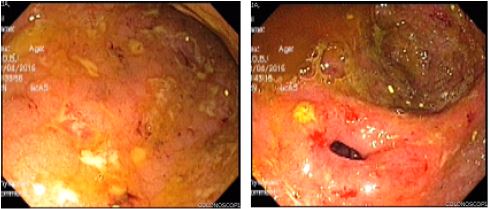

Seis meses después, la paciente reingresó por aumento del gasto fecal (hasta 10-12 deposiciones al día), anemia (con hemoglobina de 8,2 g/dl), hipoalbuminemia (2,9 g/dl) y marcada elevación de la calprotectina fecal (1074 µg/kg/heces). En la colonoscopia mostró una actividad endoscópica severa. Se decidió iniciar un nuevo ciclo de esteroides y reducción en intervalo de aplicación del biológico: adalimumab a 40mg cada semana, más azatioprina a 2mg/kg/día. Siete semanas después comenzó con diaforesis, febrículas nocturnas, adenopatías en cuello, tos seca y nuevo episodio de diarrea sin sangre (hasta 5-6 deposiciones al día). Por esta razón, se hospitalizó y se hicieron estudios donde se documentó en radiografía de tórax infiltrados intersticiales bilaterales de predominio apical; en una tomografía axial computarizada de alta resolución de tórax ( figura 4) se identificaron hallazgos sugestivos de TB pulmonar. Además, las baciloscopias en esputo fueron positivas. Se le realizó exceresis de una adenopatía del cuello donde se encontró un granuloma con necrosis central y BAAR.

Recibió tratamiento con terapia tetraconjugada (isoniacida: 300 mg; rifampicina: 600 mg; pirazinamida: 1500 mg, y etambutol: 1200 mg) en un esquema acortado supervisado. En el control del mes refería sentirse muy bien, sin síntomas generales, digestivos, ni respiratorios. Pero permaneció con adenopatías en el cuello durante casi 3 meses. La curación endoscópica se corroboró a los 6 meses de tratamiento antituberculoso. Estuvo asintomática por 14 meses, sin ningún tratamiento y con calprotectina fecal de seguimiento en 18 µg/kg/día. Luego presentó otro brote de actividad inflamatoria y elevación de reactantes y calprotectina, por lo cual se le inició tratamiento con vedolizumab en dosis de inducción a 300 mg (semana 0, 2 y 6). En la actualidad, está en tratamiento con monoterapia con vedolizumab a dosis de mantenimiento cada 2 meses. Asintomática después de 2 años de tratamiento.